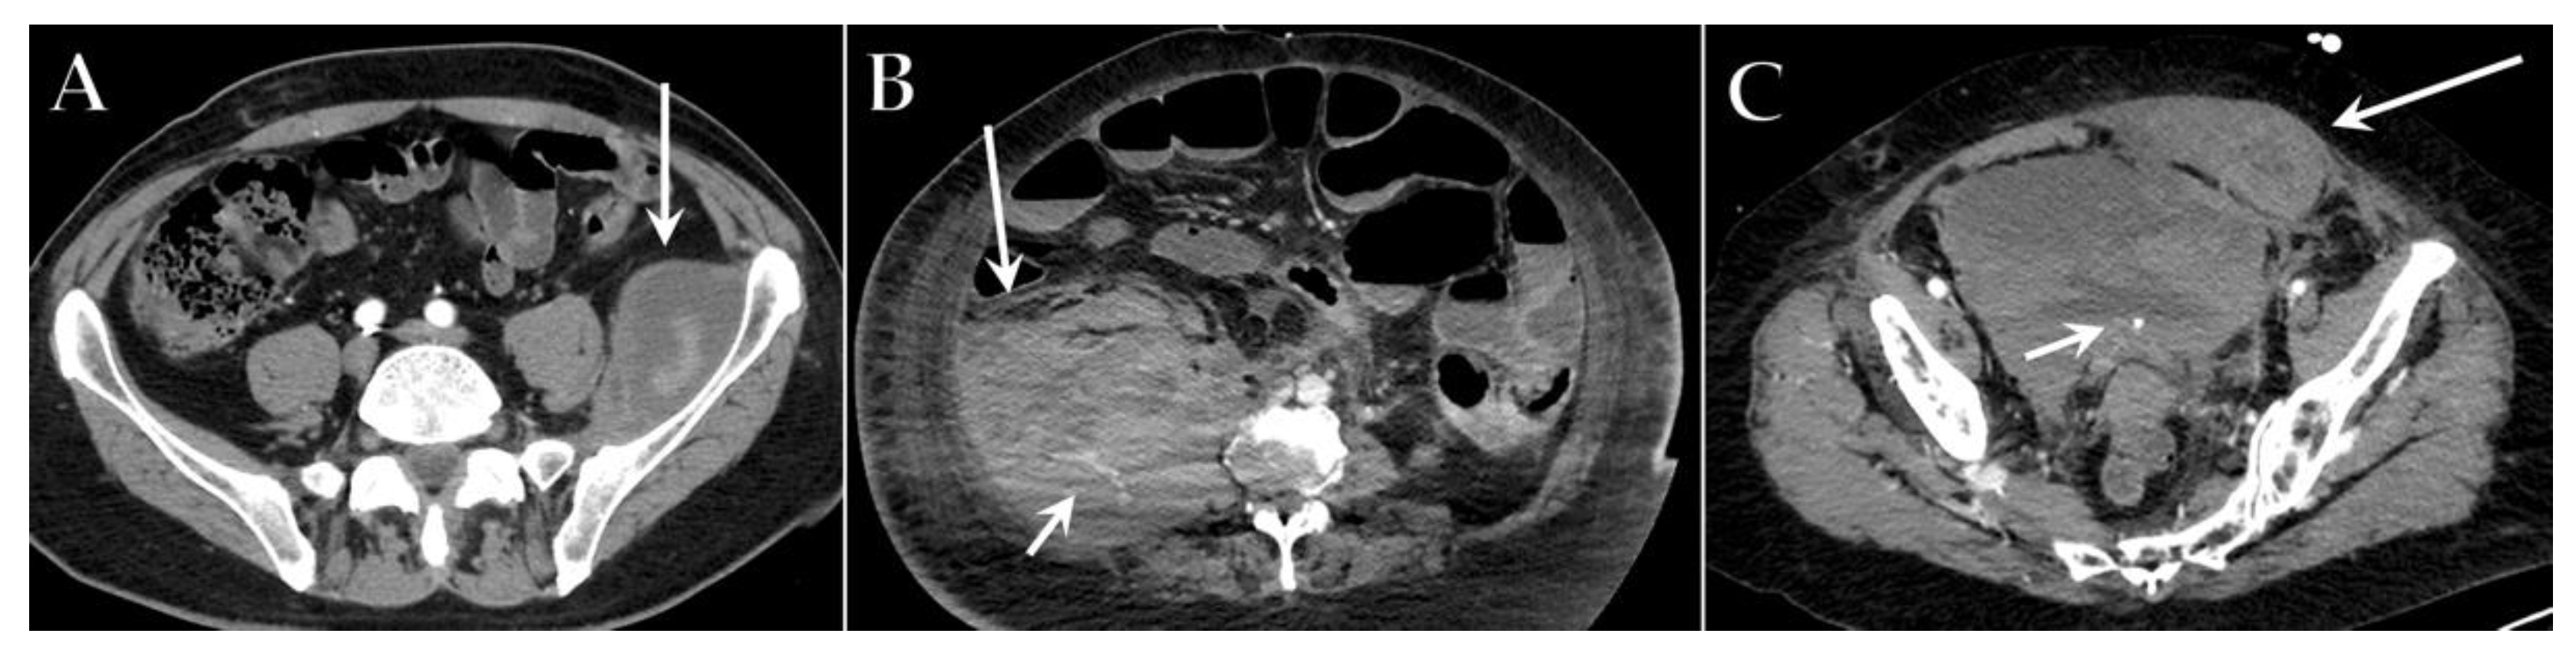

6. Vascular Complications

7. Gastrointestinal Complications